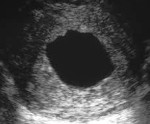

• Инструментальные методы. Информативное УЗИ с вагинальным зондом. Признаками анембриона являются плодное яйцо размером 25 мм и более и отсутствие в нем зародыша. Если через 2 недели после повторного УЗИ сердцебиение не обнаружено, диагноз анембриоза будет поставлен.

Чтобы правильно оценить результаты, УЗИ проводится в динамике. Если у плода нет сердцебиения в течение 5 недель, нельзя однозначно сказать, что была определена анемия. Отсутствие желточного мешка является неблагоприятным прогностическим признаком, который соответствует возможной анембриональной беременности.